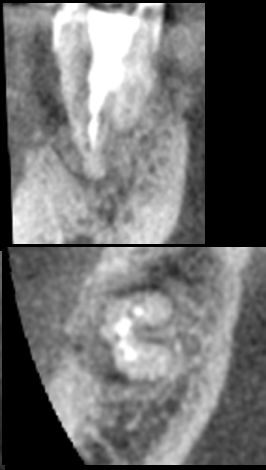

上唇の腫脹を認め、CT検査にて根尖部に嚢胞様透過像を認めた。左上の前歯が不自然に大きく噛み合わせが強くなっていたことがフレアアップの一因と考える。精密根管治療を行い、感染経路を遮断したのち歯根端切除術にて嚢胞を摘出した。

治療前

治療中

治療中